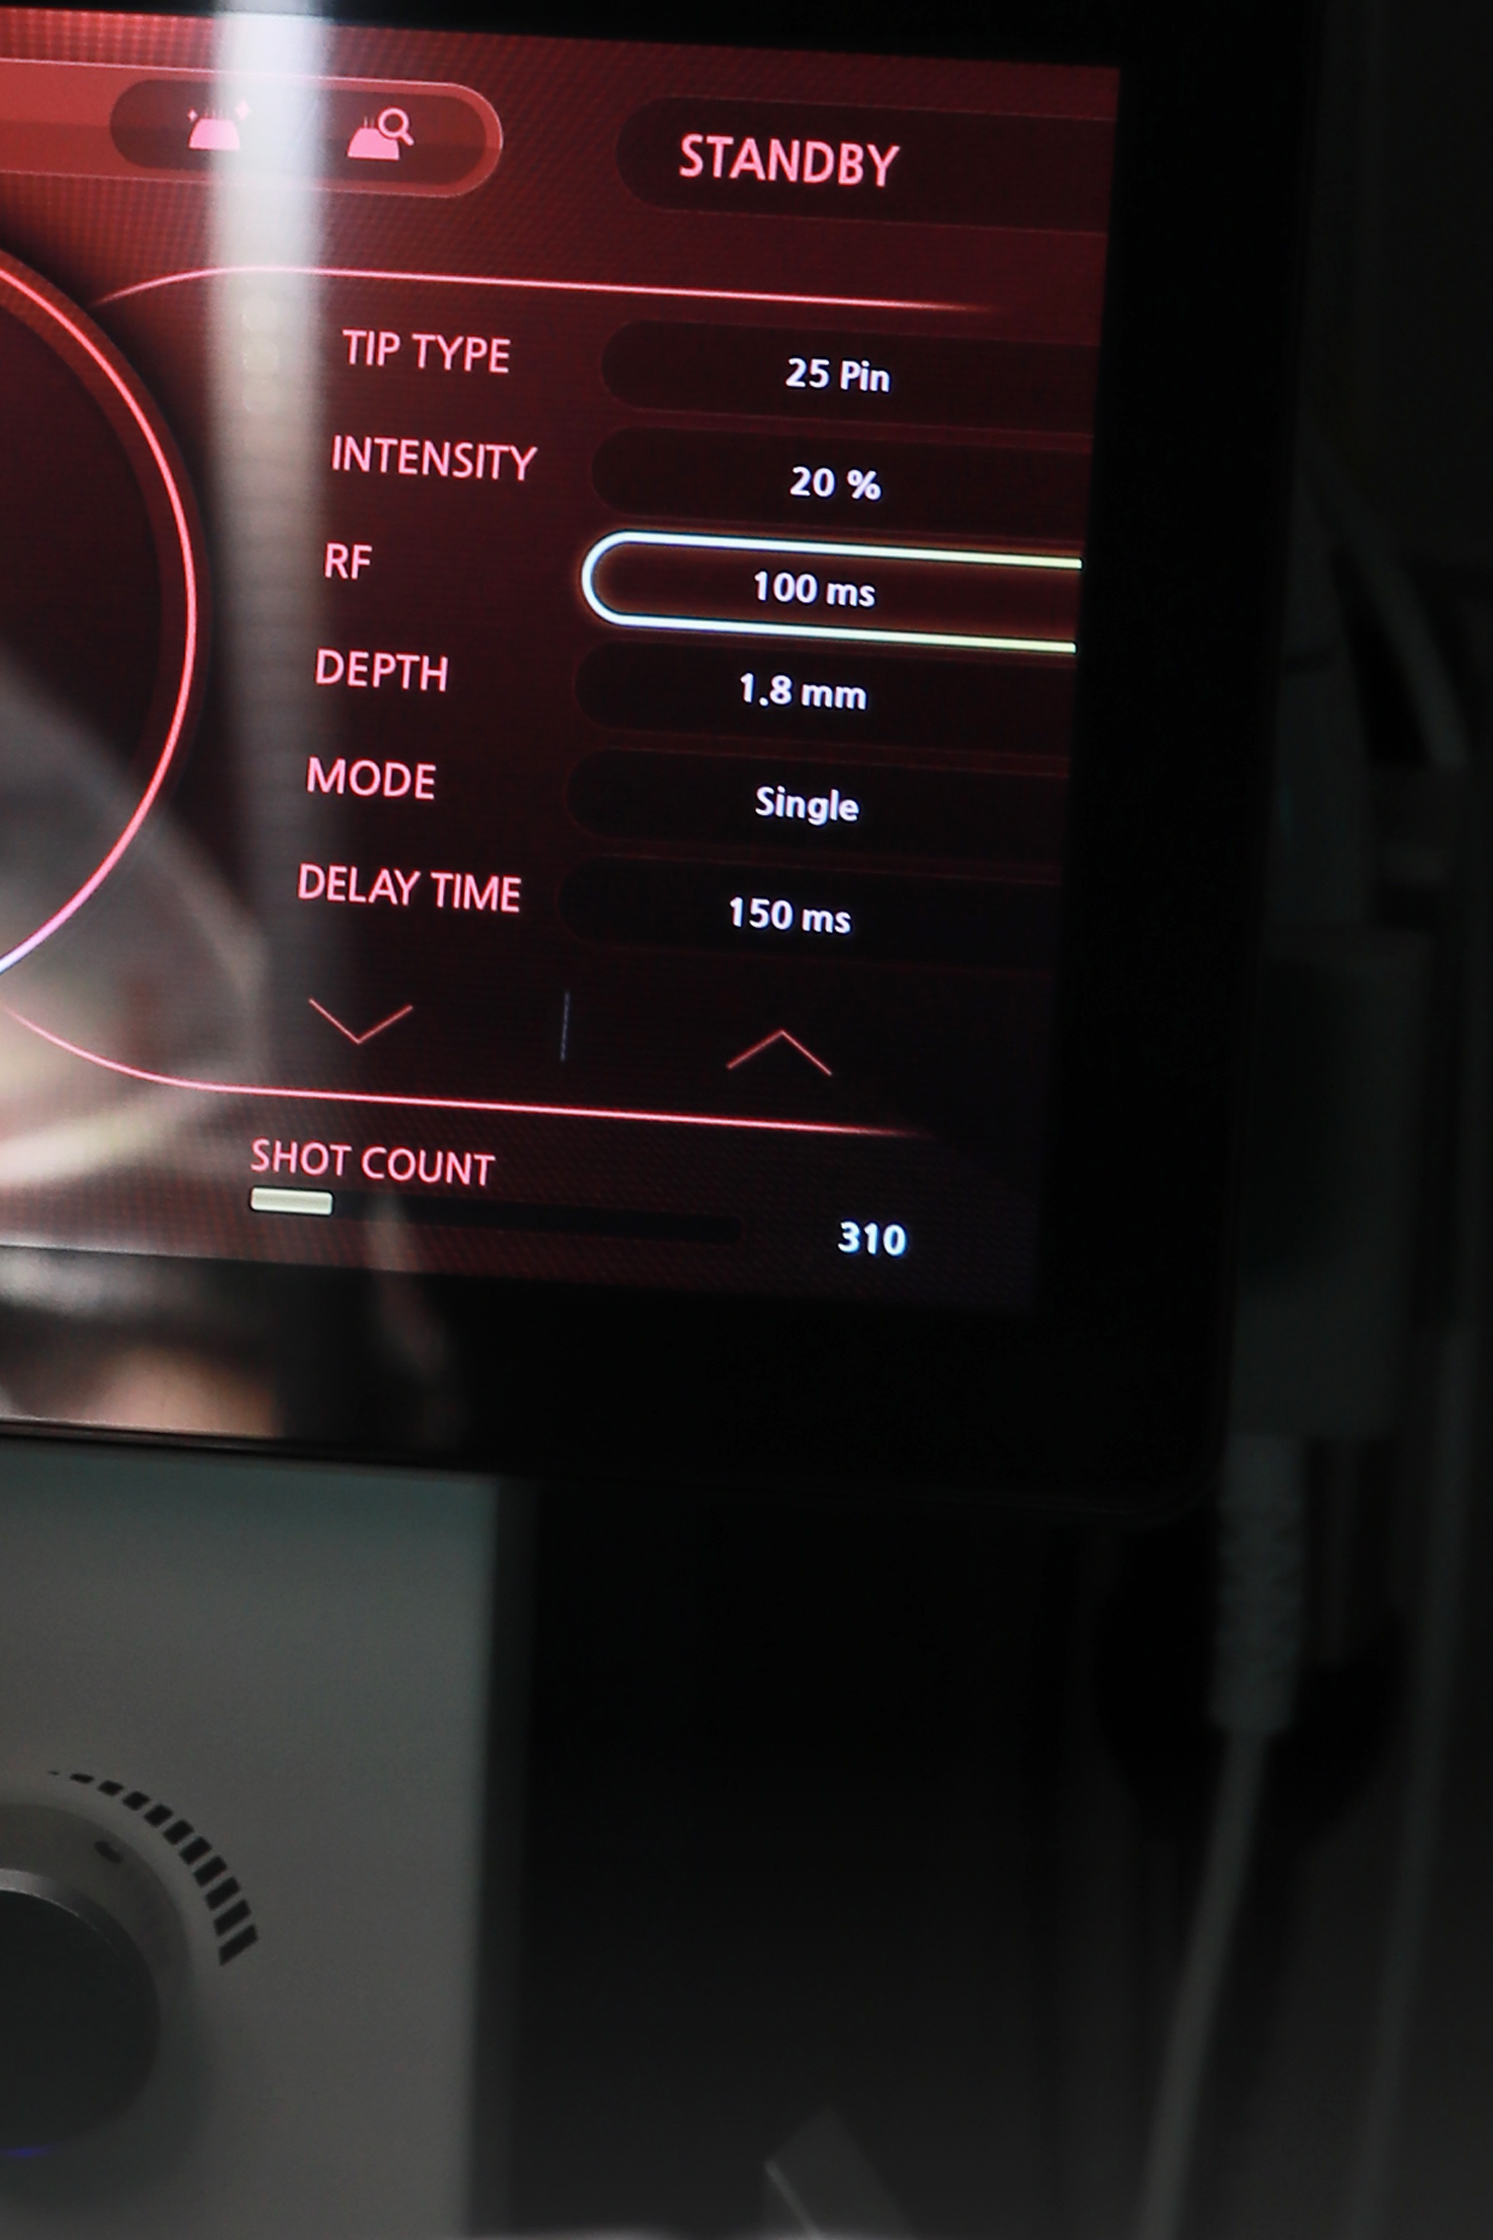

논현산부인과 헤스티아 여성의원 신사본점에 내원하시면 정확한 진단을 위한 요역동학검사를 추천드리고 있습니다. 헤스티아 여성의원 신사본점에서는 검사 기계가 마련되어 있기 때문에 요역동학검사가 가능합니다. 검사 후 맞춤형 치료를 통해 요실금을 효과적으로 개선하실 수 있었어요. 만약 복압성 요실금으로 수술을 진행하게 된다면 헤스티아 여성의원 신사본점의 수술법과 리뷰를 체크해 보시길 바랍니다. 헤스티아 여성의원 신사본점은 TOT 수술로 요도 괄약근을 받쳐 올려주기 때문에 복압에 견딜 수 있게 되며 증상 재발을 막아주는 효과가 있어요.

TOT 수술은 같은 수술이어도 증상 개선 정도가 병원마다 차이가 나게 돼요. 헤스티아 여성의원 신사본점은 요실금 수술 건수도 상당하며 의료진의 수술 노하우가 매우 풍부합니다. 요도를 지지해 주는 테이프를 삽입하고 수술 부위에 잘 고정시켜주고 있어서 요실금 증상이 재발하는 것에 대해 방지 효과가 높고 수술 부위에 부작용이 생길 확률도 매우 낮습니다.